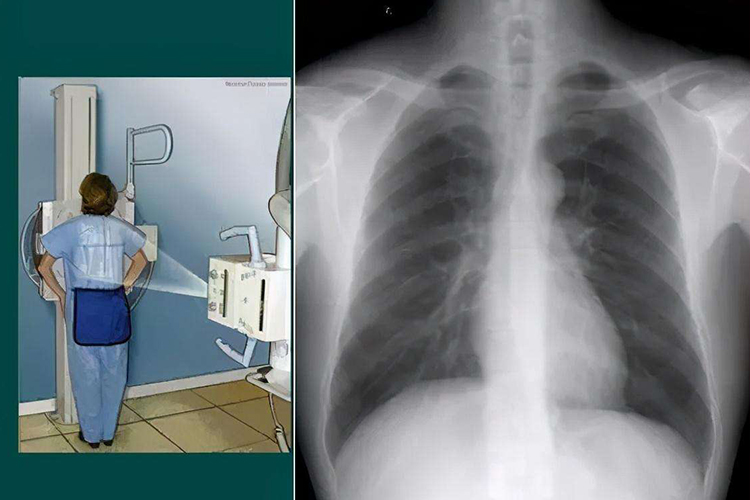

拍胸片能够帮助医生观察到肺部的许多问题,是肺部疾病初步筛查的重要工具之一,但也有其局限性。

- 胸片是一种常用的影像学检查方法,可以检测出肺部的许多异常情况。例如,可以发现肺部较大的肿块、明显的炎症浸润、胸腔积液、气胸、肺气肿、肺结核病灶等。

- 但是胸片对于一些较小的病变、早期病变或者位于肺部深部、纵隔等部位的病变,可能显示不清晰或无法发现。

- 与其他更先进的肺部影像学检查方法如胸部CT相比,胸片的分辨率相对较低。CT能够提供更详细、更准确的肺部结构信息,对于微小病灶的检测更为敏感。

- 但胸片具有操作简便、辐射剂量相对较低、价格相对便宜等优点,在初步筛查肺部疾病、病情随访以及一些特定情况下仍具有重要的价值。

拍胸片可以为医生提供关于肺部的一些重要信息,但对于某些复杂或不典型的肺部问题,可能需要结合其他检查方法如CT、磁共振成像(MRI)、支气管镜检查等,以更全面、准确地评估肺部状况。